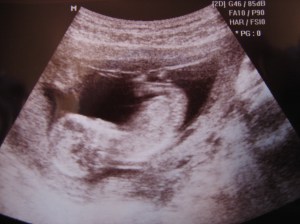

Såååå kos! Babyen vår var mer beskjeden og lå å krøka sammen beina så vi ikke skulle se om det var jente eller gutt 😛

hehe.. Lille trollet lå mye på siden også, så fikk ikke sett om det var jente eller gutt. Men en venninne som jobber som sykepleier sa senere at ut fra det hun så på bildene var hun 90% sikker på at det er jente, så blir spennende å se på neste UL om hun har rett 😉